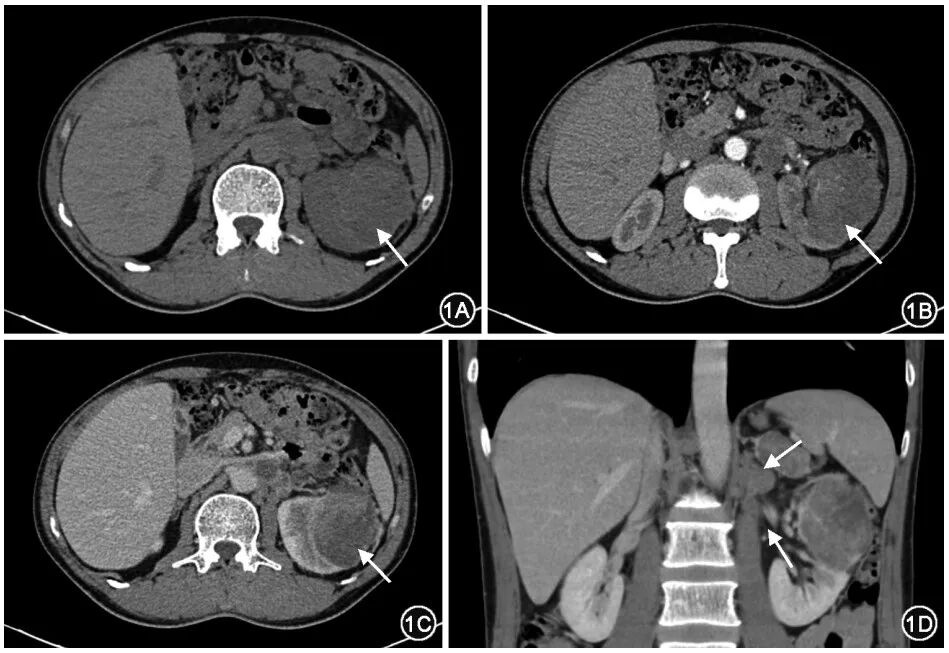

FH-RCC发病年龄较轻,平均发病年龄40~46岁。绝大部分肿瘤在CT影像上呈囊实性病变(图1),偶尔也可表现为纯实性病变[2-3],增强扫描表现为渐进性强化。初诊时常合并腹膜后淋巴结和(或)远处转移[2–4],远处转移部位包括骨、纵隔和颈部淋巴结、肝脏、肾上腺、肺及胸膜等(图1)。对于临床初诊囊实性肾脏占位病变的患者,尤其是年轻患者,建议进行胸部及全腹部CT增强扫描。如果病变实性成分表现为渐进性强化,合并腹膜后淋巴结转移或远处转移,应高度警惕FH-RCC,对这类患者应加行颈部CT增强扫描和SPECT,发现颈部肿大淋巴结和骨转移病灶,并明确全身转移情况。此外,PET-CT也对明确患者的全身转移情况具有一定价值。部分研究结果显示,特殊磁共振序列如血氧依赖磁共振(blood oxygenation level-dependent MRI,BOLD-MRI)或磁共振波谱扫描(magnetic resonance spectroscopy,MRS),对区分FH-RCC与其他可表现为渐进性强化的囊实性病变具有一定价值,可作为进一步提示FH-RCC的探索方向:FH-RCC有氧糖酵解效应明显,局部铁蛋白含量较低,其实性成分在BOLD-MRI中的R2*值会明显降低,有别于CT表现为渐进性强化的其他肾细胞癌;FH-RCC肿瘤中延胡索酸明显增多,MRS中延胡索酸对应的波峰明显增高[5]。

图1  延胡索酸水合酶缺陷型肾细胞癌典型CT增强扫描影像:平扫(1A)、动脉期(1B)和静脉期(1C)轴位图像可见肿瘤病灶呈囊实性,渐进性强化(箭头所示);1D示冠状位多平面重建可见肾门及腹膜后多发淋巴结转移(箭头所示)

【共识1】对于临床初诊囊实性肾脏占位病变患者,尤其是年轻患者,首先建议进行胸部及全腹部CT增强扫描;如果病变表现为渐进式强化,需要警惕FH-RCC的可能。如初诊或确诊FH-RCC后发现转移,需要警惕颈部淋巴结转移的可能,建议除常规行胸腹部CT增强扫描外,应加行颈部CT增强扫描(75%)。建议开展临床研究,探索BOLD-MRI、MRS和PET-CT作为FH-RCC辅助影像学诊断手段的价值(75%)。